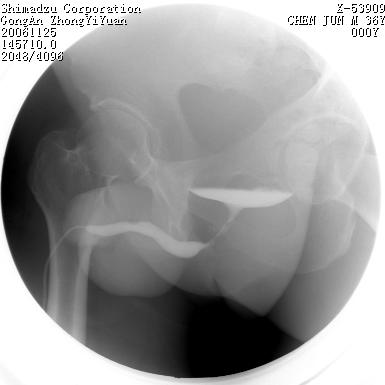

男 66岁 排尿困难半年;此人腹腔及腹膜后积液.

尿道充盈缺损,考虑占位.

后尿道内充盈缺损;前列腺结石。

后尿道狭窄,其中可见充盈缺损,我认为应先排除结核.

后尿路精阜水平充盈缺损,考虑结石或占位病变可能,建议mri检查,精阜水平尿路周围条索状密度增高影,考虑造影剂逆流入输精管或周围静脉。